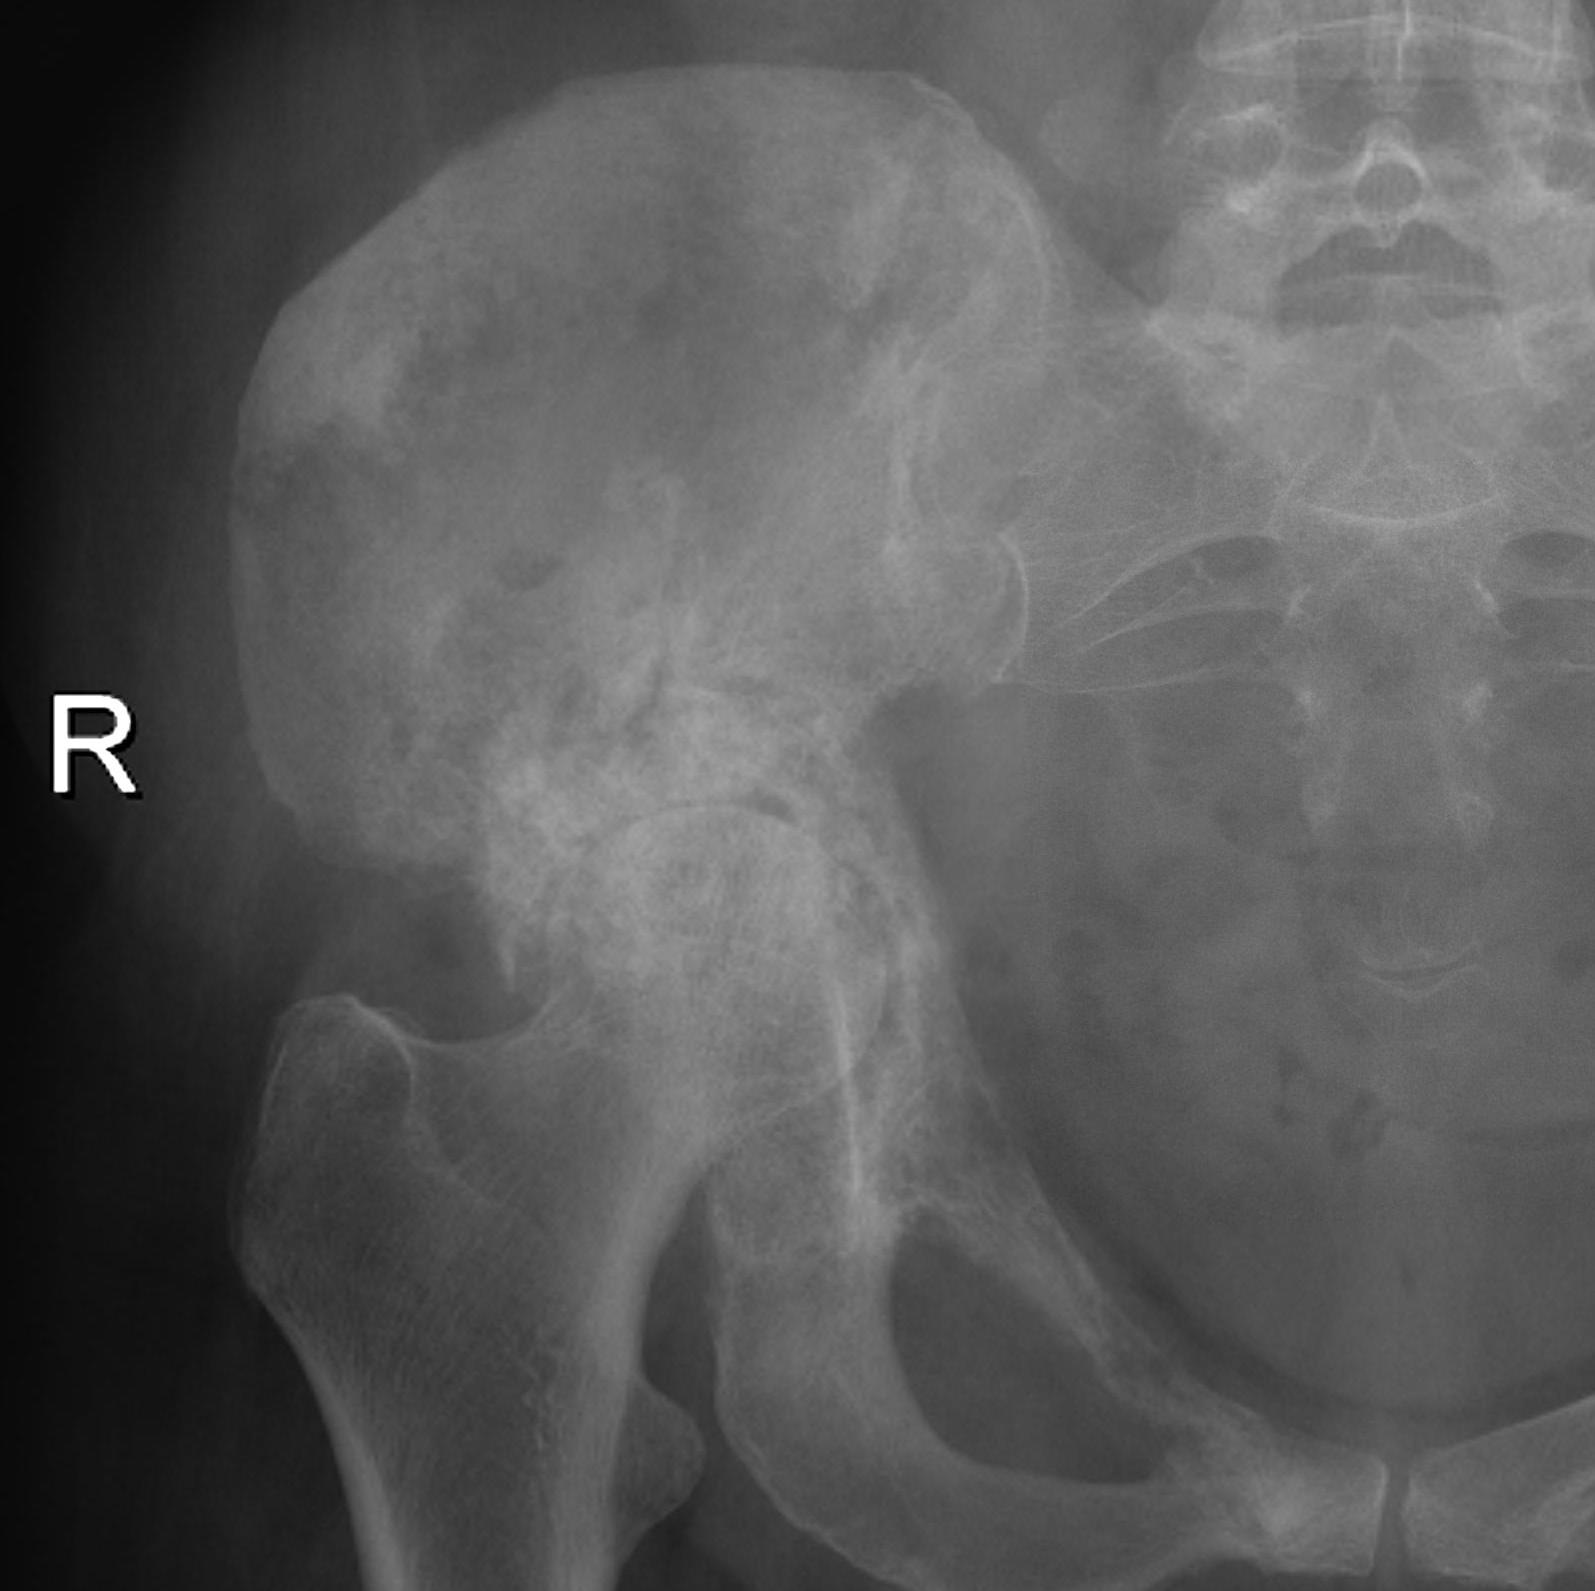

Acetabular Metastasis

Harrington classification

| Type II |

Major deficit in medial wall Rim intact |

| Type III | Massive deficit in lateral wall & superior cortex |